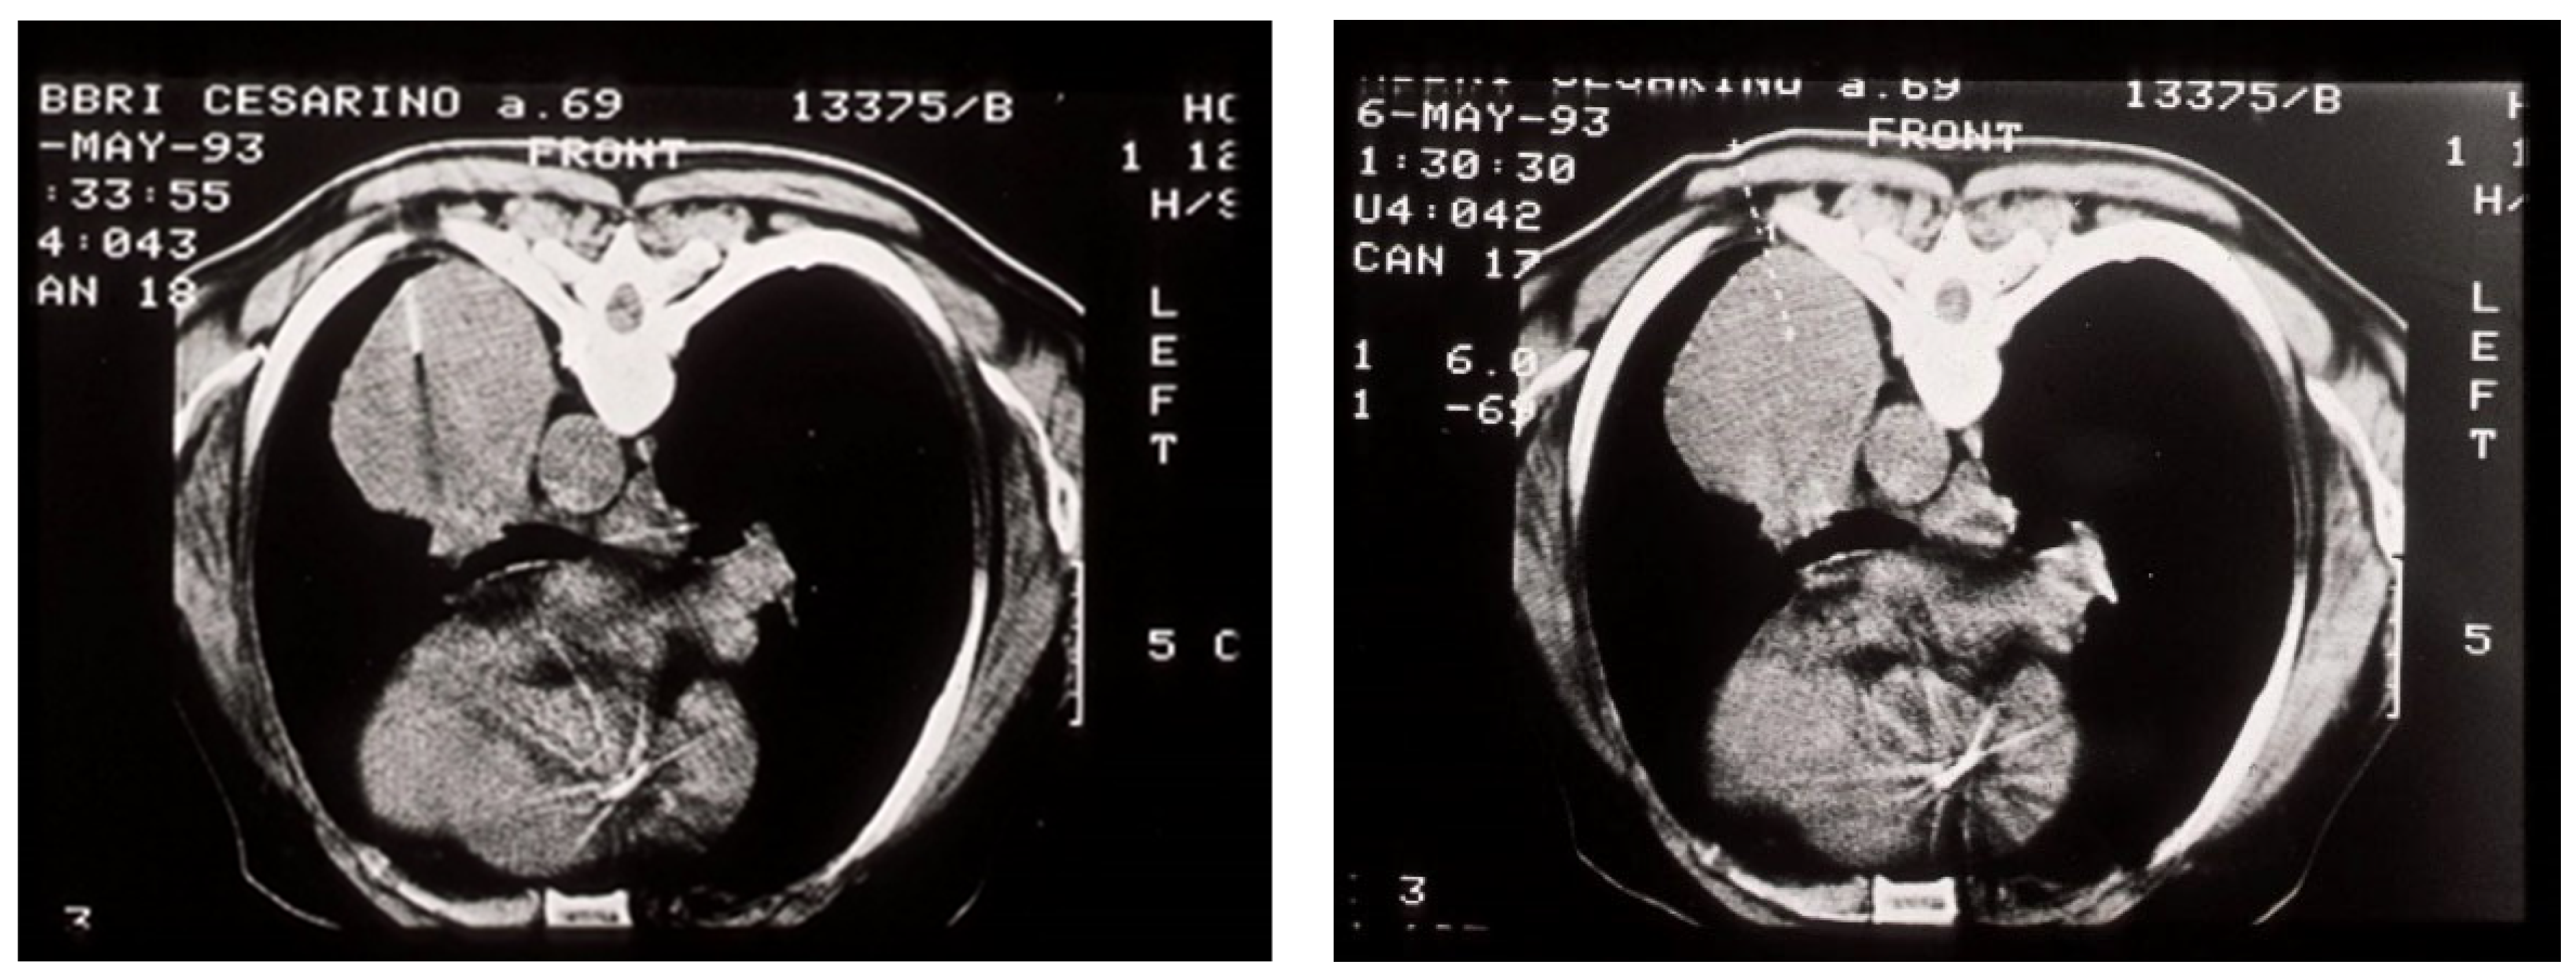

4. Mediastinoscopy and Molecular Testing

- Fu, Y.; Chen, Q.; Yu, Z.; Dong, H.; Li, X.; Chen, Q.; Hu, B.; Li, H.; Miao, J. Clinical application of ultrasound-guided mediastinal lymph node biopsy through cervical mediastinoscopy. Thorac. Cancer 2021, 12, 297–303. [Google Scholar] [CrossRef]

| Mediastinoscopy | Biopsy | 80–95% | It is not set correctly; it depends on the size of the sample |